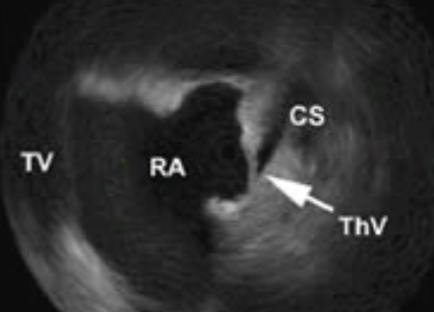

Thebesian Valve

a flap of endocardial tissue that guards the Coronary Sinus opening into the RA

often continuous w/ the Eustachian valve

not typically referenced in clinical practice